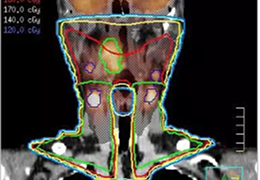

• Pinnacle³ 基于模型的轮廓勾画

基于模型的轮廓勾画可以使器官和解剖结构的轮廓勾画变得更...

计划软件